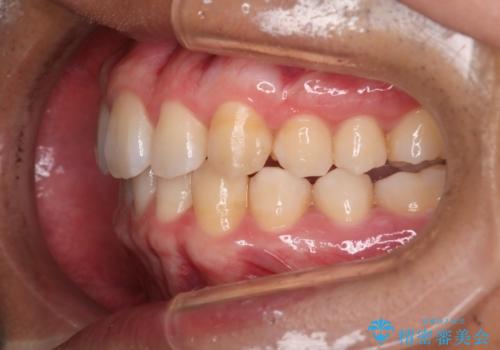

- 上の歯が出ているのが気になるのを主訴にご来院されました。人前で話すお仕事をされており目立たないマウスピース治療を希望されていました。

口元のEラインは気にならないとのことだったのでインビザラインにて治療していくことにしました。

IPR(歯と歯の間を削る処置)と歯列拡大をすることで前歯を少し下げ、がたつきを改善していく治療計画を立てました。

上の前歯が出ているという主訴が綺麗に改善されました。

その他の部位のがたつき、奥歯の噛み合わせも以前と比べると良くなっています。